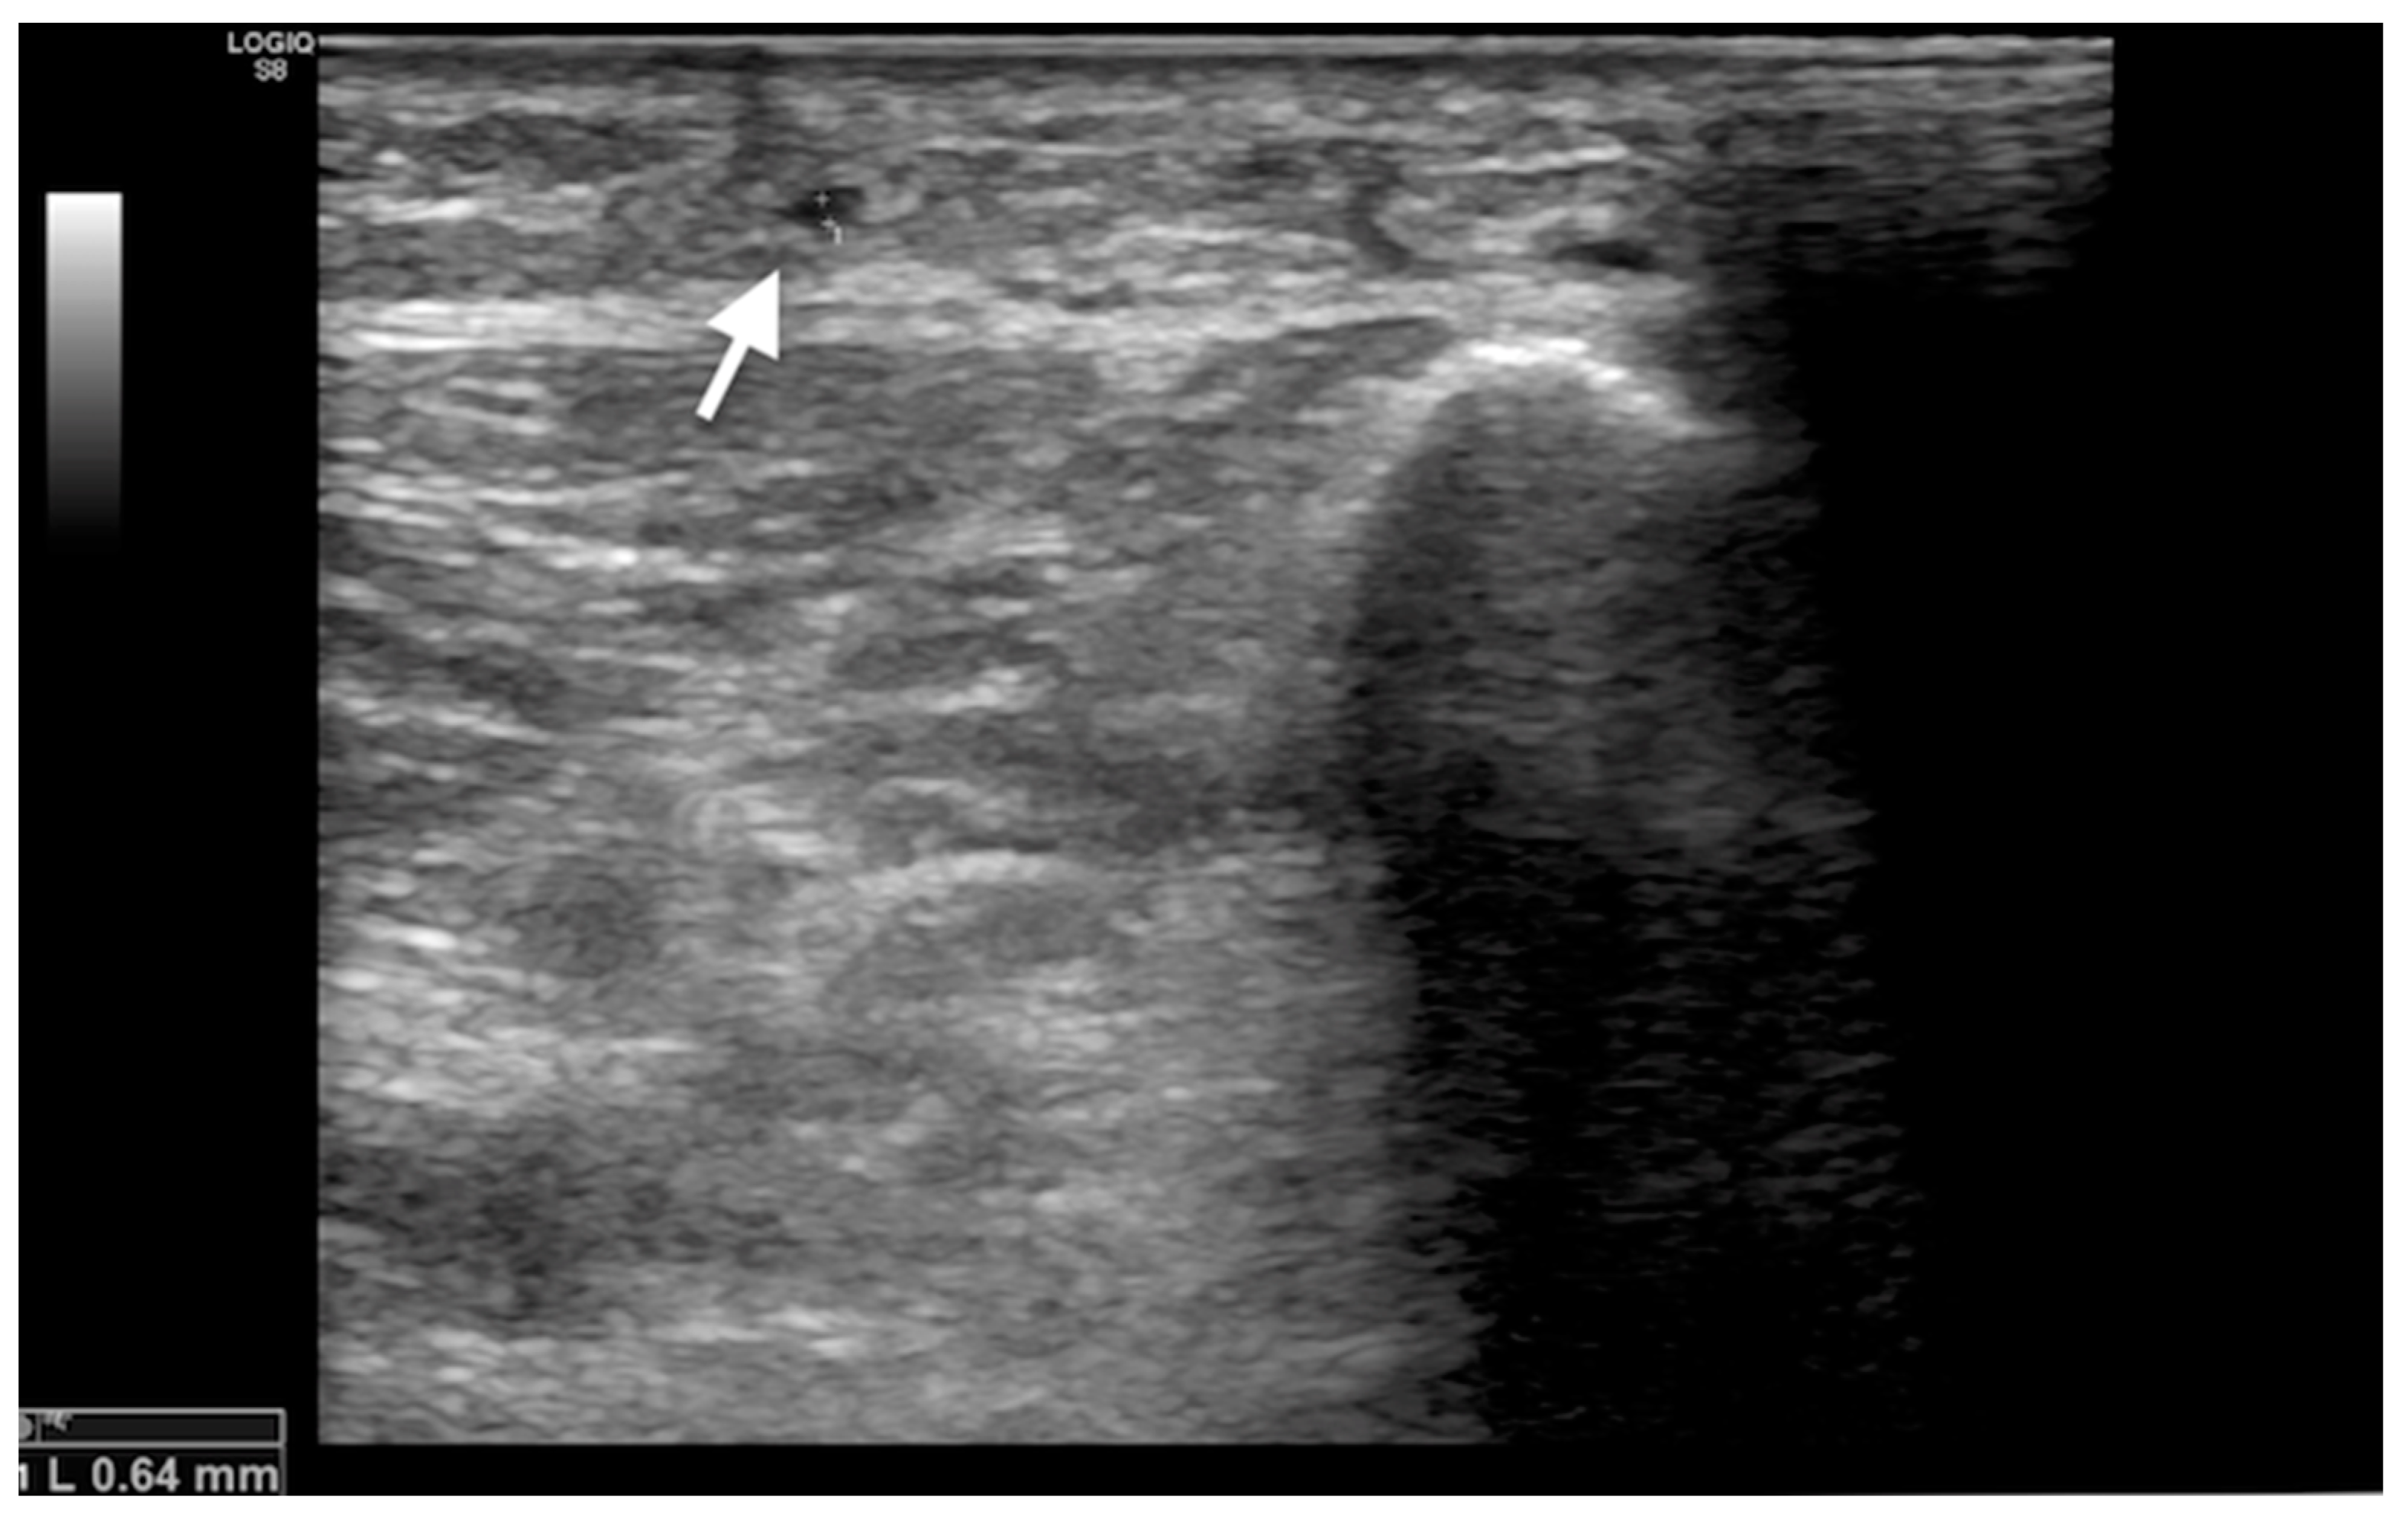

2.4. Procedure of Lumbar Sympathetic Block